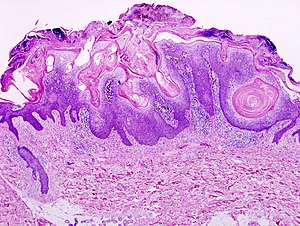

Seborrheic keratosis. H&E stain. | |

| LM | horn cysts, pigmented basal layer, hyperkeratosis |

Microscopic

Features:[2]

- Raised above skin surface.

- Border sharply demarcated.

- Hyperkeratosis - stratum corneum extra thick.

- Horn cysts - intraepidermal collections of keratin - key feature.

- Actually invaginations - not true cysts; thus, they may more accurately be called pseudohorn cysts.[4]

- Clusters of cells with brown granular material in the superficial dermis/dermoepidermal junction - pigmented melanocytes.

- Acanthotic seborrheic keratosis - thickened stratum spinosum; thick epidermis.

- Digitated seborrheic keratosis - papillomatous projections, architecture mimics a verruca.

- Stucco keratosis - pointed papillomatous projections.